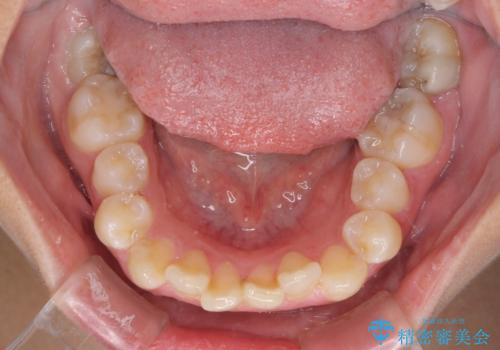

- 前歯のデコボコと歯肉に埋もれている奥歯を気にして来院された患者様です。

インビザラインでの治療を希望されていましたが、左右の下顎大臼歯が歯肉に埋もれており、特に右側は歯軸が顕著に傾斜していたため、インビザライン単独での治療は困難と判断し、ワイヤー装置を併用することとしました。

ワイヤー装置での下顎臼歯改善には時間がかかることが予想されたため、下顎のワイヤー矯正と並行して上顎をインビザラインで整え、その後インビザラインにより上下歯列を整える矯正治療を行うこととしました。

ワイヤー装置を併用したことで、レントゲン写真からも分かるとおり歯軸をしっかりと改善させることができました。